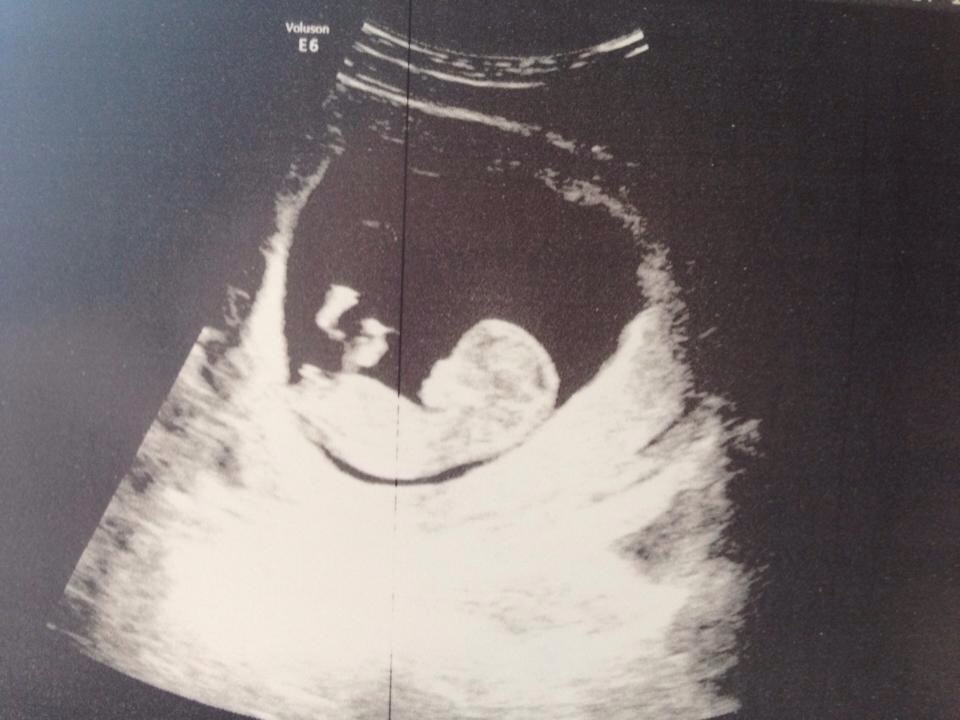

This picture is from 11w2d so too early to tell based on the nub theory, so I'd love some guesses based on the skull theory. Thanks!!Attachment 17120

I am leaning boy

I would say boy :)